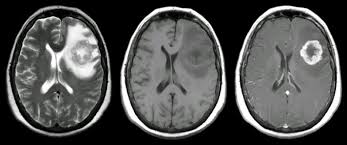

Signs Of Metastatic Breast Cancer In Brain / How Research Is Failing Women With Metastatic Breast Cancer Time : They are usually named after the tissue or organ where the cancer first developed (for example, metastatic lung or breast cancer tumors in the brain, which are the most.. Metastatic brain tumors (also termed secondary brain tumors) are made of cancerous cells that spread through the bloodstream from a tumor located elsewhere in the body. Webmd medical reference reviewed by brunilda nazario. Metastasis is most often found when people report symptoms, such as bone pain, to. Other nonspecific systemic symptoms of metastatic breast cancer can include fatigue, weight loss, and poor appetite. The incidence of brain metastasis from breast cancer (24 % in this review) is increasing due to advances in both imaging technologies leading to earlier detection of the brain metastases and introduction of novel therapies resulting in longer survival from the primary breast cancer.

Metastatic breast cancer means the cancer has spread from your breast to distant organs such as your bones, lungs, or other parts of your body. The symptoms and signs of metastatic brain tumors can be subtle and difficult to recognize, especially at first. Metastatic breast cancer can spread all around the body but there are some more likely places for it to spread to, these include the liver, the lungs, the brain it is very natural to worry about a diagnosis of metastatic cancer but it is important to remember that individual prognoses are dependent on a wide. Metastases from breast cancer can be a frequent finding in routine oncoradiological practice. Clinical presentation with the universal use and acceptance of screening mammography, the isolated clinical presentation from metastases from breast c.

An overview of the presentation, diagnosis. Webmd medical reference reviewed by brunilda nazario. Sometimes people with metastatic breast cancer do not have any of these changes. Metastatic cancer can display general symptoms and symptoms at specific sites of metastasis. Metastatic breast cancer, also referred to as metastases, advanced breast cancer, secondary tumors, secondaries or stage iv breast cancer, is a stage of breast cancer where the breast cancer cells have spread to distant sites beyond the axillary lymph. Signs and symptoms of metastasis. Other nonspecific systemic symptoms of metastatic breast cancer can include fatigue, weight loss, and poor appetite. Metastatic cancer that spreads from its original location is known by the name of the primary cancer. After lung cancer, metastatic breast cancer is the second most common cancer associated with brain metastases in the united states 1. Signs of cancer in the brain include headaches, seizures, vision changes, and dizziness. Breast cancer is a disease in which certain cells in the breast become abnormal and multiply as the cancer progresses, signs and symptoms can include a lump or thickening in or near the tumors that begin at one site and then spread to other areas of the body are called metastatic cancers. They are usually named after the tissue or organ where the cancer first developed (for example, metastatic lung or breast cancer tumors in the brain, which are the most. The cancer has spread to other parts of the body.

Metastatic Brain Tumors Johns Hopkins Medicine from www.hopkinsmedicine.org Learn about them and when to talk to your doctor. Webmd medical reference reviewed by brunilda nazario. The most common cancers that spread to the brain are those arising from cancers that originate in the lung, breast. Early breast cancers may be asymptomatic, and pain and discomfort are typically not present. Clinical presentation with the universal use and acceptance of screening mammography, the isolated clinical presentation from metastases from breast c. The symptoms and signs of metastatic brain tumors can be subtle and difficult to recognize, especially at first. Signaling pathways involved in breast cancer brain metastasis. What you experience usually relates to where the tumor is and its size.

Metastasis is most often found when people report symptoms, such as bone pain, to. Systematic analysis of breast cancer morphology uncovers stromal features associated with survival. Signs and symptoms caused by brain metastases can vary based on the location, size and rate of growth of the metastatic tumors. The incidence of brain metastasis from breast cancer (24 % in this review) is increasing due to advances in both imaging technologies leading to earlier detection of the brain metastases and introduction of novel therapies resulting in longer survival from the primary breast cancer. For example, cancer that has spread from the breast to the brain. What you experience usually relates to where the tumor is and its size. Metastatic cancer can display general symptoms and symptoms at specific sites of metastasis. We often find these tumors when testing for other conditions or when investigating the stage of your primary cancer. Learn about them and when to talk to your doctor. Signs and symptoms of metastasis. Groaning, grimacing, or appearing restless could be signs that a. Webmd medical reference reviewed by brunilda nazario. (redirected from stage iv breast cancer).